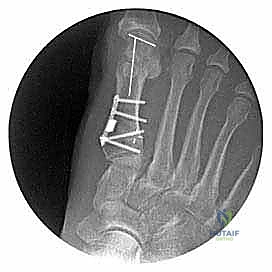

الخطوة الخامسة: وضع الطعم العظمي والتثبيت (Fixation)

بمجرد الوصول إلى التصحيح المثالي، يتم ملء الفجوة الوتدية بطعم عظمي (غالباً ما يؤخذ من البروز العظمي الذي تمت إزالته في الخطوة الثانية، أو استخدام طعم عظمي صناعي/من بنك العظام).

لضمان التئام العظم في هذا الوضع الجديد، يقوم الأستاذ الدكتور محمد هطيف بتثبيت القطع العظمي باستخدام تقنيات التثبيت الداخلي الحديثة، مثل:

* شريحة معدنية دقيقة مخصصة (Low-profile Plate) من التيتانيوم مزودة بمسامير.

* أو مسامير ضغط مجوفة (Cannulated Screws).